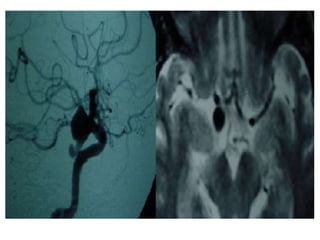

• #7 Aneurysm: axial T2-wi (a) shows a heterogeneous and enlarged right cavernous sinus with a multilayer appearance (black arrows) corresponding to a giant intracavernous aneurysm. Note the mass effect on the right temporal lobe. See also the 3D volume rendering showing the aneurysm (b).

• #8 Cavernous ICA Aneurysm.

• #9 Right posterior communicating artery aneurysm digital angiography and MR.

• #10 Intracavernous aneurysms. A, Axial T2-weighted image shows a left intracavernous ICA (A) aneurysm. Note flow artifacts (arrow) confirming the pulsatile nature of the lesions. B, Coronal postcontrast maximum-intensity image from a CT angiogram in the same patient shows the left intracavernous aneurysm.